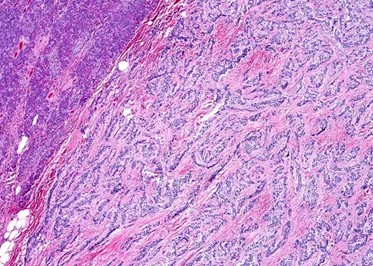

Caso 3

Mujer de 36 años que ingresa a Hospital Sanatorio Franchin el 11 de octubre de 2023 de forma programada para realización de duodeno pancreatectomía cefálica por tumor de cabeza de páncreas en estudio. Refiere hallazgo de lesión en forma incidental durante estudio de control hace dos meses por presentar antecedentes familiares (neoplasia endocrina múltiple). Se interna para manejo quirúrgico. Estudios de tomografía revelan formación nodular localizada en cabeza y cuerpo pancreático de paredes gruesas que mide 24 x 28 mm, que en resonancia se muestra hiperintensa en T2 y realce periférico luego de la administración de contraste endovenoso. Presenta restricción en la difusión con caída de la señal ADC, por lo que se vincula con una lesión de alta celularidad.

Tomografía de abdomen y pelvis con cte ev: del 13/10/2023.

Complicaciones posquirúrgicas

Tomografía de abdomen con cte ev: del 20/10/2023.

Tomografía de abdomen con cte ev: del 26/10/2023.

Estudio histopatológico reveló neoplásica de estirpe neuroendocrina bien delimitada.

La resonancia magnética es el otro estudio de imagen no invasivo que nos permite la detección de la lesión con una sensibilidad mayor que la de la tomografía, del 85% al 95%, donde los insulinomas presentan un realce tras la administración de contraste con gadolinio y secuencias T1 sin contraste son lesiones hipointensas y en secuencias T2 son hiperintensas.

La resonancia magnética confirmó aún más el diagnóstico de las lesiones ya previamente visualizadas en tomografía en esta revisión, con realce de las lesiones en secuencias T1 y contraste con gadolinio, y en las secuencias funcionales con restricción de la lesión y caída de la señal en el mapa de ADC.